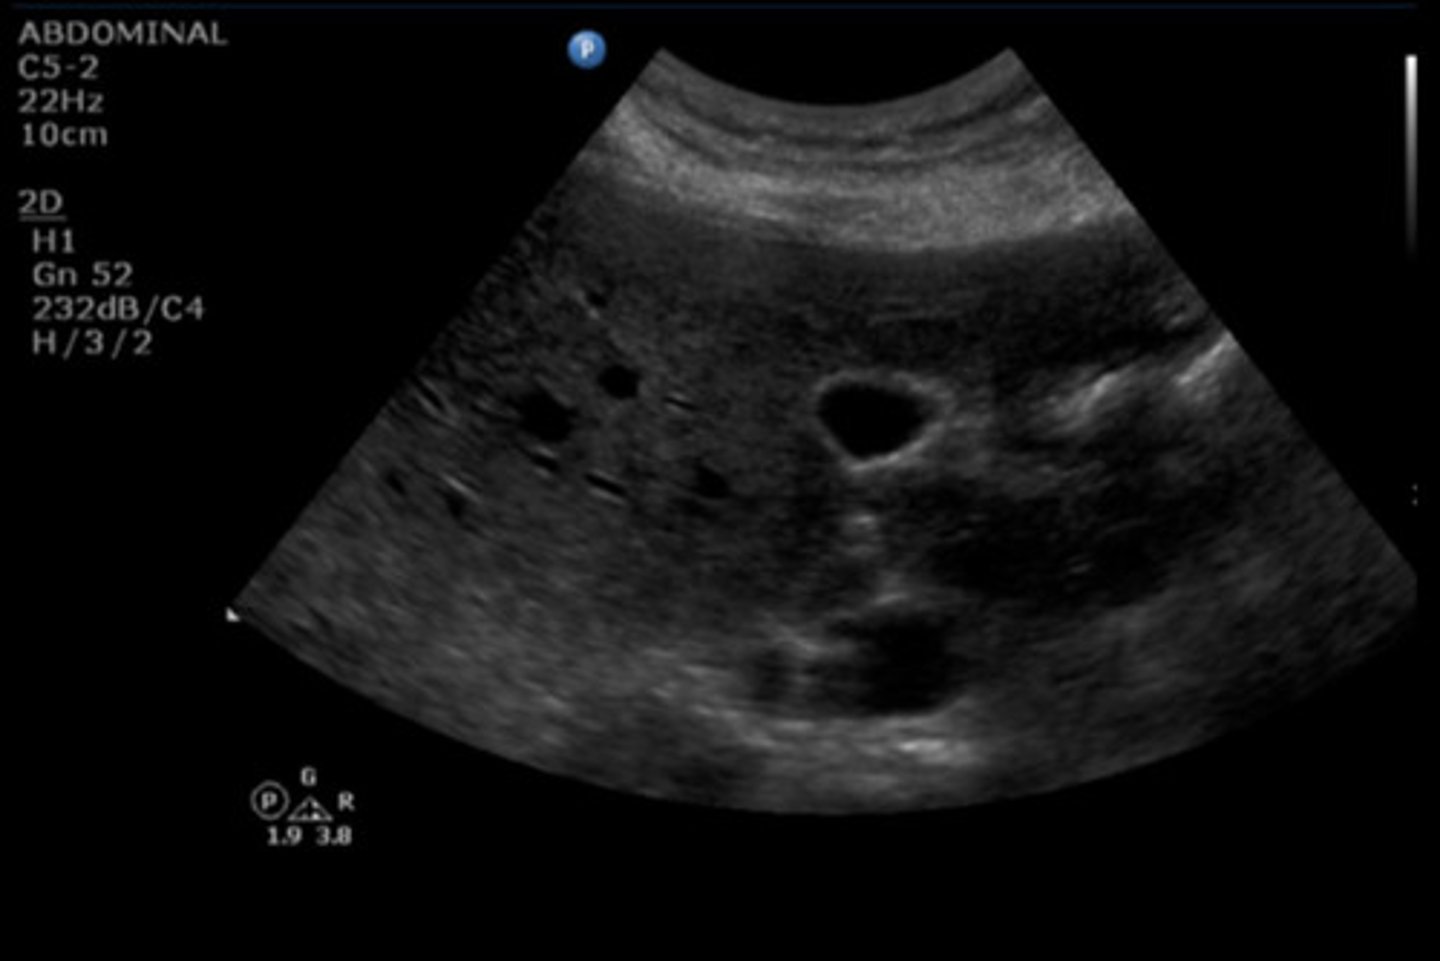

8

New cards

CBD

Identify the following;

<p>Identify the following;</p>